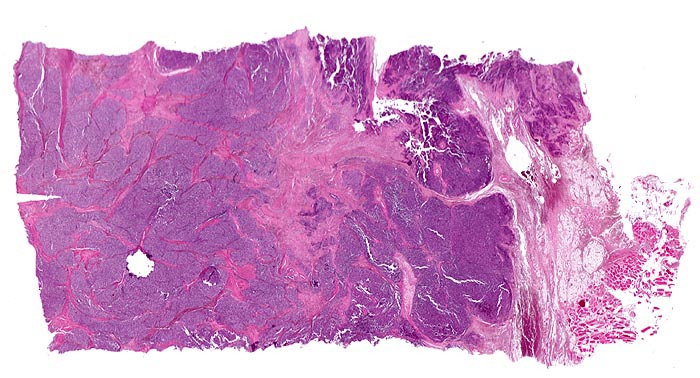

PathoPic – image database / PathoPic ID 4517 - Ewing-Sarkom

Ewing-Sarkom

Lobulierter Tumor bestehend aus zelldichten soliden Tumorplatten umgeben von Bindegewebssepten. Die Begrenzung ist scharf. In unmittelbarer Nachbarschaft des Tumors sind Fettgewebe und Skelettmuskulatur erkennbar.

Femuramputat mit festem grauweissem intraossärem feucht-glänzendem Tumorgewebe. Die extraossäre Weichteilkomponente ist weicher und brüchiger. Der Gewebsschnitt stammt aus der extraossären Weichteilkomponente.